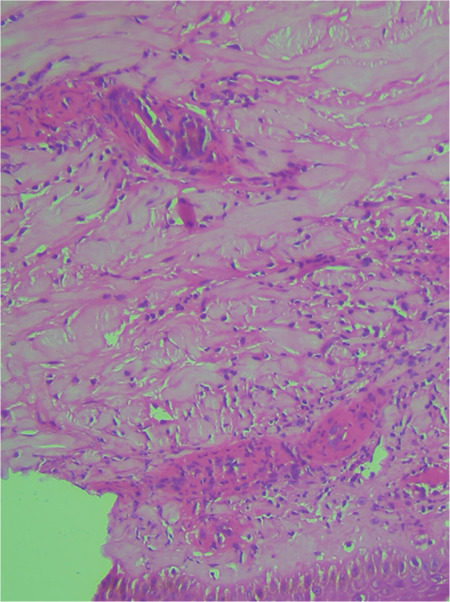

一名慢性淋巴细胞白血病患者的伊布替尼相关白细胞坏死性血管炎

Ibrutinib-Associated Leukocytoclastic Vasculitis in a Patient with Chronic Lymphocytic Leukemia.